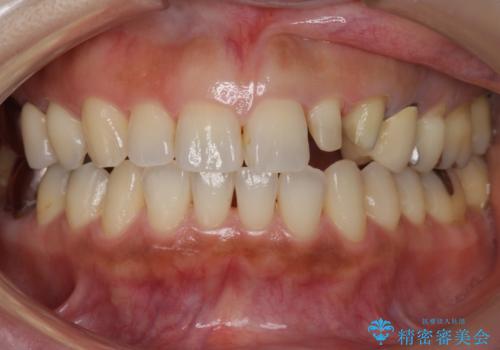

前歯が左右対称じゃない 保険の被せ物をきれいにしたい ホワイトニング併用

- 25万円 内訳 左上23:ジルコニアクラウン(スペシャル)各10万円、仮歯 各1万円、オフィスホワイトニング(エクセレント)3万円費用は治療当時の料金となります

左右対称に仕上げることができ、治療には非常に満足していただきました。